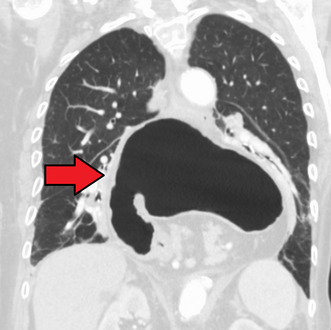

يتم تشخيص فتق الحجاب الحاجز عادةً من خلال سلسلة تصوير الجهاز الهضمي العلوي، التنظير الداخلي، قياس الضغط عالي الدقة، مراقبة درجة حموضة المريء، والتصوير المقطعي المحوسب. يسمح ابتلاع الباريوم كما في سلسلة تصوير الجهاز الهضمي العلوي لرؤية حجم المريء وموقعه وتضيقه. كما يمكنه تقييم حركات المريء. يمكن للتنظير الداخلي تحليل السطح الداخلي للمريء بحثاً عن التآكلات والقرح والأورام.

وفي الوقت نفسه، يمكن لقياس الضغط تحديد سلامة حركات المريء ووجود ارتخاء المريء. وتسمح اختبارات الأس الهيدروجيني بالتحليل الكمي لنوبات الارتجاع الحمضي. كما أن التصوير المقطعي المحوسب مفيد في تشخيص مضاعفات الفتق الحجابي مثل الالتواء المعدي، واسترواح الصفاق، واسترواح المنصف.[8]